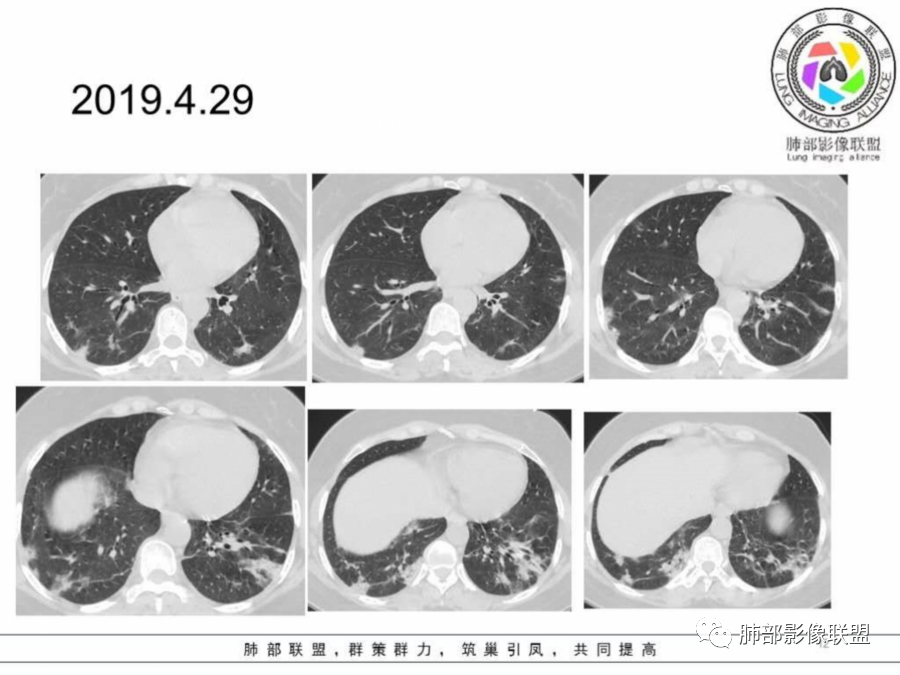

胸CT:4月23:双下肺渗出影,以外周胸膜下为主,4月29日病灶增多,部分沿支气管血管束分布,渗出影病灶密度较前增高。

胸CT:4月23日:支气管血管束及胸膜下分布实变及磨玻璃影,4月29日病灶增多。

两肺胸膜下外周为主多发磨玻璃影、实变影,非叶段分布,间质受累,抗感染治疗效果不佳。

女,50岁,双眼睑肿胀一月,活动后气促10余天,双肺胸膜下多发斑片及结节状高密度影,部分病灶沿支气管血管束分布,右肺病灶内见小空洞影,考虑自身免疫性疾病,病毒性肺炎。

4月23日两肺叶位于胸膜下分布多发散在斑片状磨砂影,内见细网格征,4月29复查对比,大部份病灶收收,范围减少,且边缘平直,内收;考虑病毒肺炎!

这个病变其实也就是周围间质的病变,有细网格征及碎石路征,这是典型的OP样改变,外围胸膜下,下肺明显,有一定的此起彼伏,影像只能判断到OP。